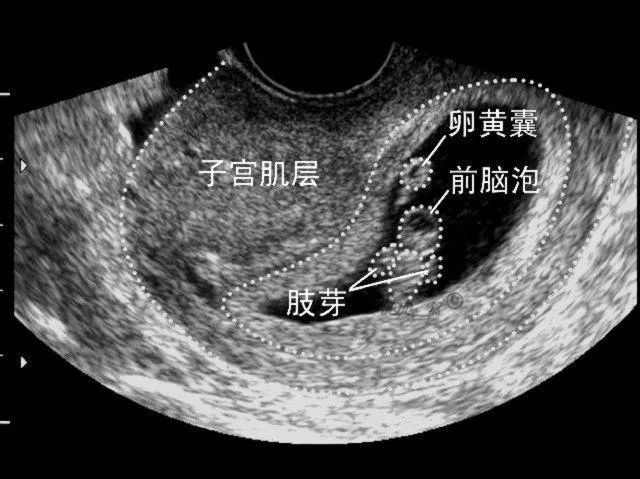

B超检查方便、安全、费用低,检出符合率高。用它来检查盆腔,可尽早发现内生殖器有无畸形盆腔有无炎性包块输卵管是否存在积液,有没有子宫肌瘤、子宫腺肌症、卵巢囊肿,以及子宫内膜厚度是否均匀等。

妇科B超有两种,腹部B超和阴道B超。